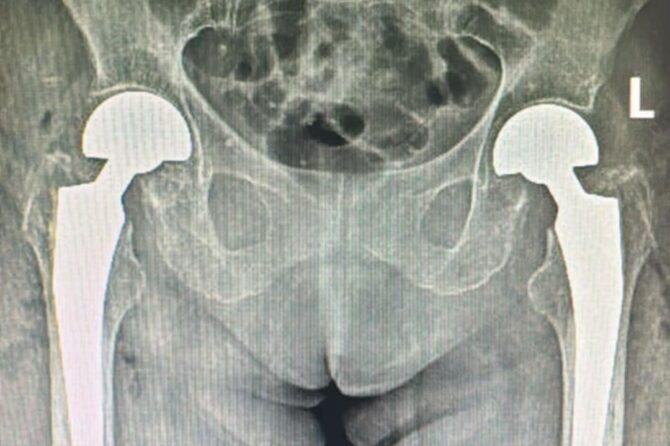

Premieră medicală în județul Sibiu: artroplastie bilaterală de șold realizată într-un singur timp operator, la SCJUS DESCARCĂ DOCUMENT